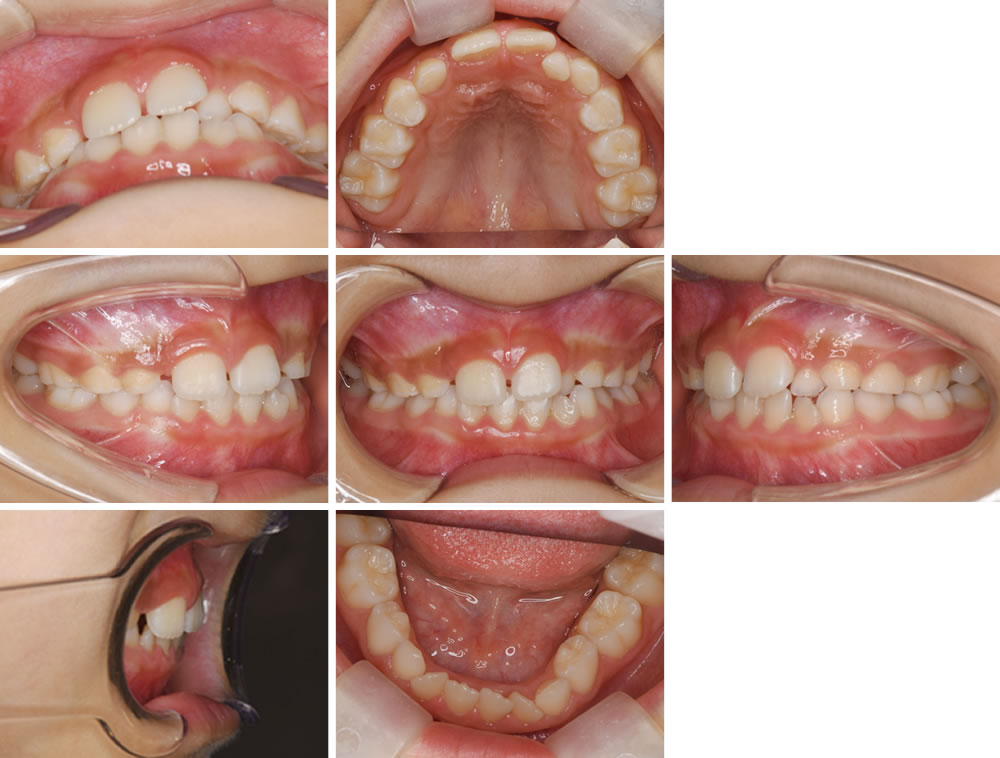

こちらの患者さまは、歯並びが気になるとの主訴で来院されました。将来のことも考え、小児矯正で骨格や歯並びを改善する計画を立てました。